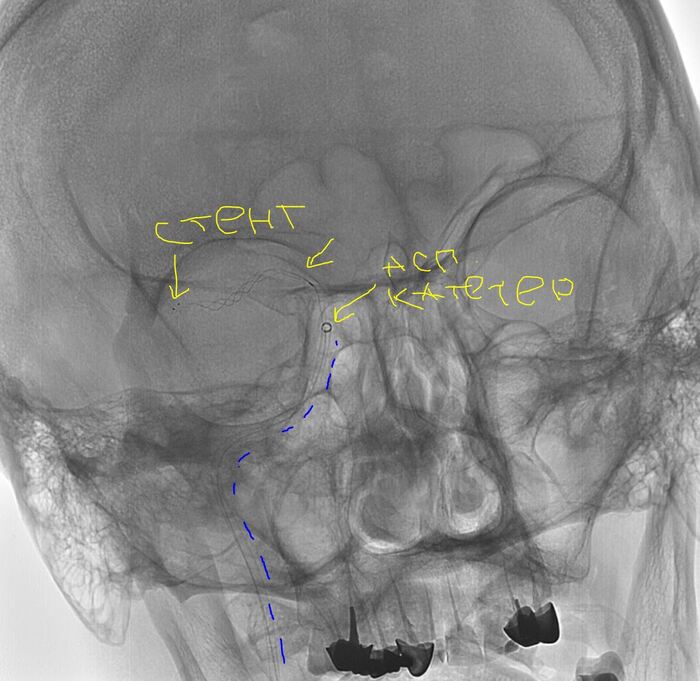

Далее гайд катетер вместо диагностики, с учетом характера поражения решаю выполнить комбинированную методику = аспирационный катетер с одновременным использованием стента ретривера (усиленная методика ВСТЭ, я ее предпочитаю). Делаю т.н. "матрешку" = в гайд аспирационник, далее микрокатетер и проводник для реканализации и заведения "микрика". Все получилось без особых усилий. После заведения микрокатетера провел стент ретривер (для извлечения тромба), раскрыл его, удалив микрик, заякорился и максимально, как мог подвел на аспирации аспирационный катетер (картинка ниже)